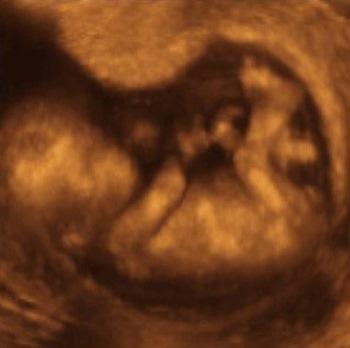

En la ecografía 3D se ve el bebé de manera bastante nítida y con volúmen, es como hacer una fotografía del bebé en la que se pueden apreciar sus características.

En cambio en la ecografía 4D se captan las imágenes de la misma manera pero es posible montarlas de manera que se pueda observar el movimiento del feto en tiempo real.

La diferencia es que en la ecografía 5D se puede jugar con la iluminación y el contraste de la imágen, por lo que se puede apreciar con mucha más claridad lo que está haciendo el feto ahí dentro.

La encargada de la imágen jugaba con la iluminación y podíamos verle más o menos definido según el momento.

Pudimos apreciar sus rasgos faciales y como ahí dentro parecía estar cómodo. Por solamente eso ya creo que valió mucho la pena.

Te dejo el vídeo de mi ecografía 5D para que puedas apreciar exactamente de lo que hablo.